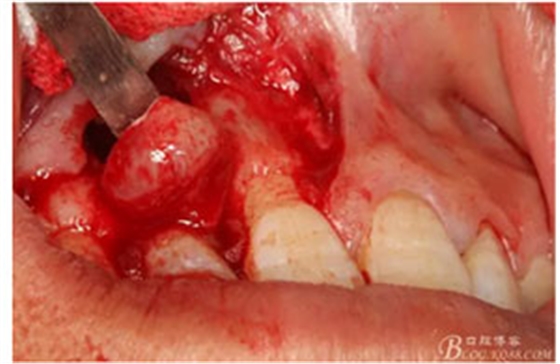

圖8.從垂直切口和水平切口的連接處翻瓣。發(fā)現(xiàn)11和12之間的骨壁有缺損。

圖9.翻開角形瓣后,有骨壁缺損,囊壁有穿孔,這就是溢膿的竇道出口。